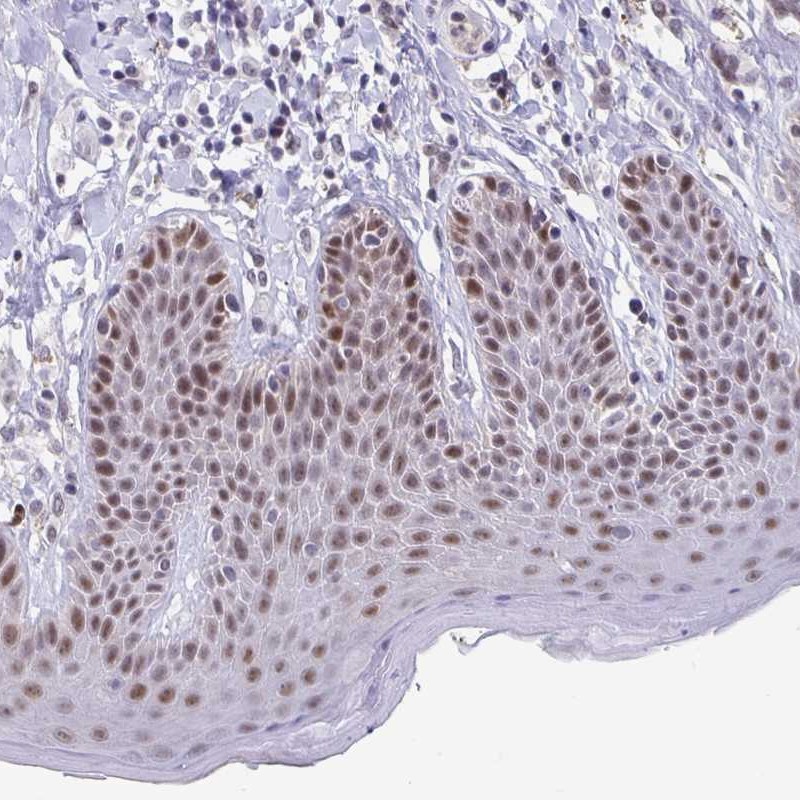

Immunohistochemical staining of human skin shows moderate nuclear positivity in epidermal cells.